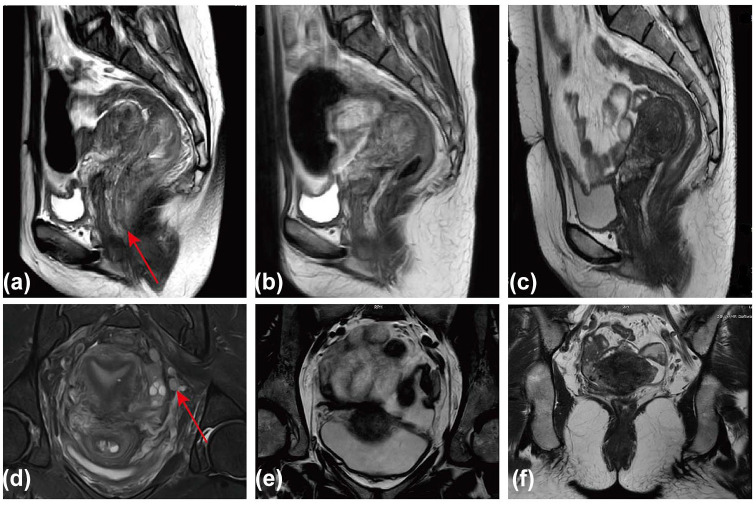

超低局部晚期直肠癌由于其解剖学上的限制和对传统新辅助治疗的有限反应,对保留括约肌手术提出了重大挑战。本病例报告描述了一位诊断为IIIb期(cT3N2M0)超低位直肠癌的患者,他强烈倾向于保留括约肌。考虑到标准治疗在实现肿瘤充分降期方面的效果欠佳,我们实施了一项为期6个月的综合新辅助治疗方案,包括光动力治疗(PDT)、化疗、靶向治疗和免疫治疗。PDT选择性诱导肿瘤坏死,破坏肿瘤血管,增强治疗剂渗透,将肿瘤微环境转化为免疫应答状态。这种多模式入路导致肿瘤明显消退,有利于保留括约肌的根治性切除。术后病理检查证实病理完全缓解,患者无疾病,无进展生存期超过48个月。该病例强调了多模式治疗方法的潜力,将PDT与全身治疗相结合,可以增强肿瘤分期,增强免疫治疗的疗效,并提高超低局部晚期直肠癌的括约肌保存率。这种综合策略为优化这些具有挑战性的病例的临床结果提供了一种有希望的方法。

Ultra-low locally advanced rectal cancer presents significant challenges for sphincter-preserving surgery due to its anatomical constraints and limited response to conventional neoadjuvant therapies. This case report describes a patient diagnosed with stage IIIb (cT3N2M0) ultra-low rectal cancer who had a strong preference for sphincter preservation. Given the suboptimal efficacy of standard treatments in achieving sufficient tumor downstaging, a comprehensive 6-month neoadjuvant regimen was implemented, combining photodynamic therapy (PDT), chemotherapy, targeted therapy, and immunotherapy. PDT selectively induced tumor necrosis, disrupted the tumor vasculature, enhanced therapeutic agent penetration, and transformed the tumor microenvironment into an immune-responsive state. This multimodal approach resulted in significant tumor regression, facilitating sphincter-preserving radical resection. Postoperative pathological examination confirmed a pathological complete response, and the patient remains disease-free, with a progression-free survival exceeding 48 months. This case highlights the potential of a multimodal treatment approach, combining PDT with systemic therapies, to enhance tumor downstaging, potentiate the efficacy of immunotherapy, and improve sphincter preservation rates in ultra-low locally advanced rectal cancer. This integrated strategy offers a promising approach for optimizing clinical outcomes in these challenging cases.